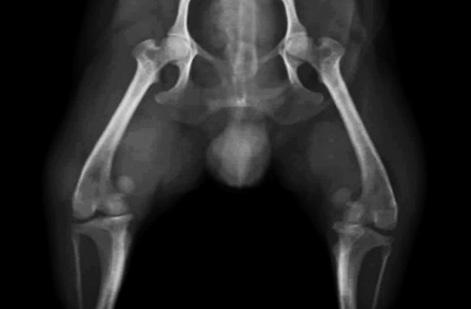

La luxación patelar o rotuliana se define como el desplazamiento de la rótula de su posición anatómica normal. La rotula o patela es un pequeño hueso que se aloja en la ranura troclear del femur, compone la porción craneal de la articulación de la rodilla, actúa como punto de apoyo aumentado el brazo de palanca del cuádriceps.

Las luxaciones rotulianas se pueden presentar de forma medial 80% y lateral 20% de los casos. La luxación patelar tiene por causas: traumatismo, roturas de ligamentos de la rodilla, predisposición genética.